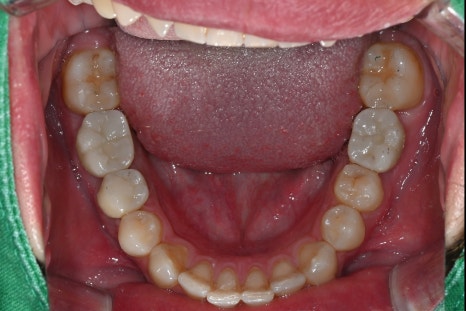

내원 당시 촬영한 위 아래 구강 내 사진입니다.

임플란트와 크라운 치료 레진 치료 모두 완료된 후의 구강 상태입니다.

기능과 심미성 모두 만족스럽게 회복되었습니다.